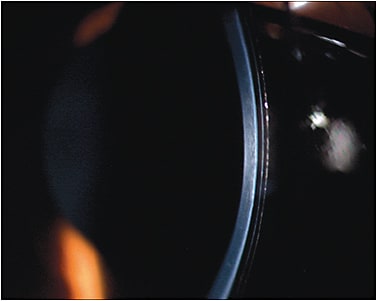

VA with the dispensed lens was 20/50 and 20/40, respectively. The lenses had an ideal fit centrally and peripherally (Figure 8). The mini-scleral lenses could be worn without problems for 12 hours without bulbar redness. After lens removal, the eye no longer had a “rebound” effect.